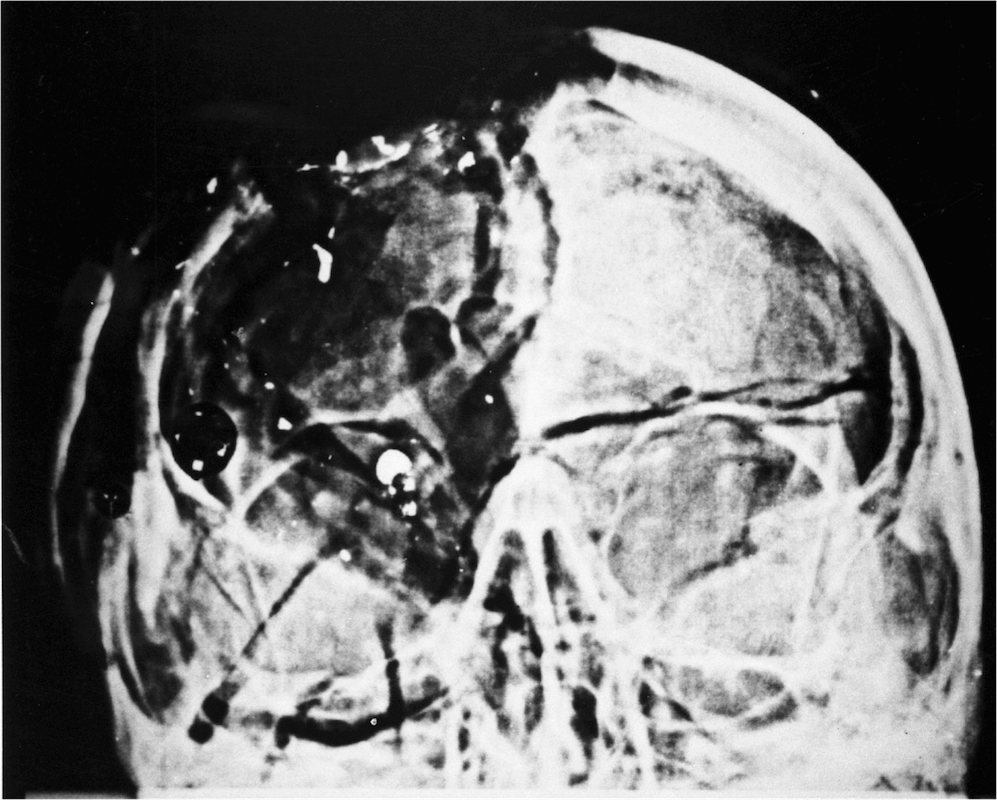

DM: This is just one more deception. After Stringer reviewed the brain photographs, he declared to the ARRB that he had not taken them. He knew this because they were the wrong film type and also because he had photographed serial sections of the brain—which no longer exist.[6] I have also demonstrated the radical inconsistency between the brain in the photographs versus the brain in the X-rays. At least one of these images must have been faked.[7]

G: “Identical images do not create such an [stereo] effect…” (356)

DM: G is here discussing stereo viewing of the autopsy photographs, which I have performed on virtually all of the photographic pairs at the National Archives. G does not say whether he has done any of this—which is a serious omission for a “critical thinker.” After all, it is not necessary to visit the National Archives to do this—as I have discussed in my online lectures. The images are available in Robert Groden’s Absolute Proof. G does not explain why he has not performed such an elementary exercise. But he is certainly correct about this: When identical images are viewed via a stereo viewer, no 3D effect is achieved. That bizarre result is precisely what is seen at the critical site at the back of JFK’s head—exactly where the Parkland physicians (and virtually everyone else) saw a large hole. Stereo viewing at that site shows only a 2D effect. And quite to the point, this absence of a 3D effect is not seen elsewhere in the autopsy collection, as I ascertained via a painstaking review of these many pairs of images. Who else has done this? So, what are the odds that—only at JFK’s occiput—a 3D effect is absent? (Robert Groden has confirmed the same observation to me.) G does not comment on this—but he has no excuse for omitting this simple exercise, which he could still do today or tomorrow, but I shall not hold my breath.

G: “…an irregular-shaped white spot near the subject’s hairline…has led these authors to suspect this was the real entrance point…Aguilar and Mantik therefore conclude that the head in the photograph is not Kennedy’s…According to Mantik, this is as close as it gets to finding a ‘smoking gun.’” (358–359)

DM: This is false—triply false. I have never believed that the white spot represented an entry wound; it is far too inferior to fit with the missing Harper fragment, which is discussed, and illustrated, in painstaking detail in my e-book, JFK’s Head Wounds. Furthermore, I have never stated that the head was not JFK’s. On the contrary, it is his head—but with the hole covered by a photographic matte insertion so as to disguise the hole. G seems unable to make such fine distinctions, which only confuses things for him, as he admits, “Confused? It seems everyone is.”

Regarding smoking guns, I would now regard my subsequent discovery of the T-shaped inscription (see the end of this review for images) as a more blatant example of a smoking gun. But G seems not to know about this, even though the T discovery was made in 2001, and I have reported it on innumerable occasions.[9]

G: “The X-rays and pictures both located the wound of entry high on the back of the head (at the cowlick), consistent with the trail of bullet fragments inside Kennedy’s skull, and of the exit wound.” (359)

DM: This is (again) triply false:

1. The radiologists could not locate a wound of entry (or of exit) on the X-rays. I agree. That was explicitly stated in their reports. Did G fail to read them?

2. All three pathologists disavowed the “red spot” as a bullet entry. Humes said, “I don’t know what that [red spot] is…. I don’t, I just don’t know what it is, but it certainly was not a wound of entrance.” (7HSCA 254) In fact, no one at Parkland had reported such a red spot.

3. The trail of bullet fragments does not even transect G’s selected cowlick entry site!

4. And G’s statement totally ignores the many tiny metallic fragments at JFK’s forehead. This is thoroughly discussed in Chesser’s online lecture, which is not cited by G.

DM: I was indeed short-sighted. My myopia in one eye reached -9 diopters, which is what allowed me to identify the double exposure inside the 6.5 mm fragment while viewing the extant AP skull X-ray at the National Archives. This was only further proof that the 6.5 mm object had been (illegally) forged via a double exposure in the dark room.[15]

DM: I have discussed McDonnel[16] and his proposed clues to X-ray alteration at length in my e-book, which G has obviously not read. Quite oddly, McDonnel did not even raise the possibility of using optical density as a tool! Furthermore, I have cited—quite specifically—how my observations do in fact meet McDonnel’s requirements. I even discovered one possibility that he had overlooked. Unfortunately, Mac passed away (not far from me on December 13, 1992) just as I was entering this case, or we would have had some fascinating conversations. I did, however, have enlightening (face-to-face and via telephone calls) conversations with Kodak’s top scientist, Arthur G. Haus, PhD, about my article on the X-ray alterations—which he read and about which he made no criticisms.[17] Also see my detailed technical references to the inspired work of Haus, which are cited in my online review of McAdams (at my website).

G: “The…6.5 mm object…seemed to have troubled none of the autopsy doctors. In fact, it was not mentioned in their report.” (371)

DM: Douglas Horne, who witnessed their ARRB testimony, observed quite the opposite effect. He reported that Humes was so frustrated that Horne expected him to walk out of his testimony at any minute. All three pathologists denied seeing this 6.5 mm object on the X-rays. Even worse, none of the dozens of participants at the autopsy (who observed these films on the view box that night) mentioned this object—which was precisely the point of taking any X-rays at all. This bogus object only surfaced with the Clark Panel Report some years later.

Of course, when I asked John Ebersole about this object, he instantly terminated any further discussion of the JFK autopsy—and never spoke of it again to anyone. What G cannot dare to address, of course, is the unanimous opinion—of all the experts—that there is no image that correlates with this unphysical object on the lateral X-ray. Such a situation transports us directly out of our known physical world.

Furthermore, on the AP skull X-ray, the front to back length of this bogus 6.5 mm object is many centimeters long (as shown by the optical density data), which is longer than all of JFK’s mercury-silver amalgams (which overlap one another on this view). Of course, G cannot afford to comment on such central conundrums, so he does not.

Moreover, how does G explain this nearly circular 6.5 mm object—one that could not be explained by John Fitzpatrick (the ARRB forensic radiologist), or by the Clark Panel, or by Larry Sturdivan (the HSCA expert)?[18] Quite astonishingly, G (per his account) is able to succeed where everyone else has failed: “…it is little more than a distraction caused by circular logic.” (371)

One final observation may be useful. Here are two images of an emulsion-based X-ray film that I own; I created the T-shaped inscription on this film. The film is similar to those used for the 1963 autopsy X-rays and the T-shape is similar to what I saw on one lateral JFK skull film. The T-shape was obviously produced by scraping emulsion off the JFK X-ray film. (The image of this lateral JFK X-ray is not in the public domain.) Recall that, at the National Archives, no emulsion is missing—on either side—of that lateral JFK skull X-ray film.

The left image above shows the missing emulsion side, while the right image displays the intact emulsion side (my film has emulsion on both sides, just as the JFK autopsy films do). The 3D visual impact (on my film) of physically missing emulsion (actually gouged into the film) can only be fully appreciated via binocular vision. This is especially dramatic when viewed at a glancing angle to the light source. I repeatedly did this while at the National Archives (for both sides of the JFK film), but no emulsion was missing anywhere.[27]

Therefore, we now know that the Archives houses only a copy of this lateral X-ray. After all, only a copy film could preserve both the T image and the emulsion. But if this a copy film, then the door stands wide open to X-ray alteration—because a double exposure could easily have intervened. Of course, we already knew that this same lateral JFK X-ray was a copy—due to the presence of the White Patch, so the T-shaped inscription is merely a second confirmation that this is not the original lateral skull X-ray of JFK.